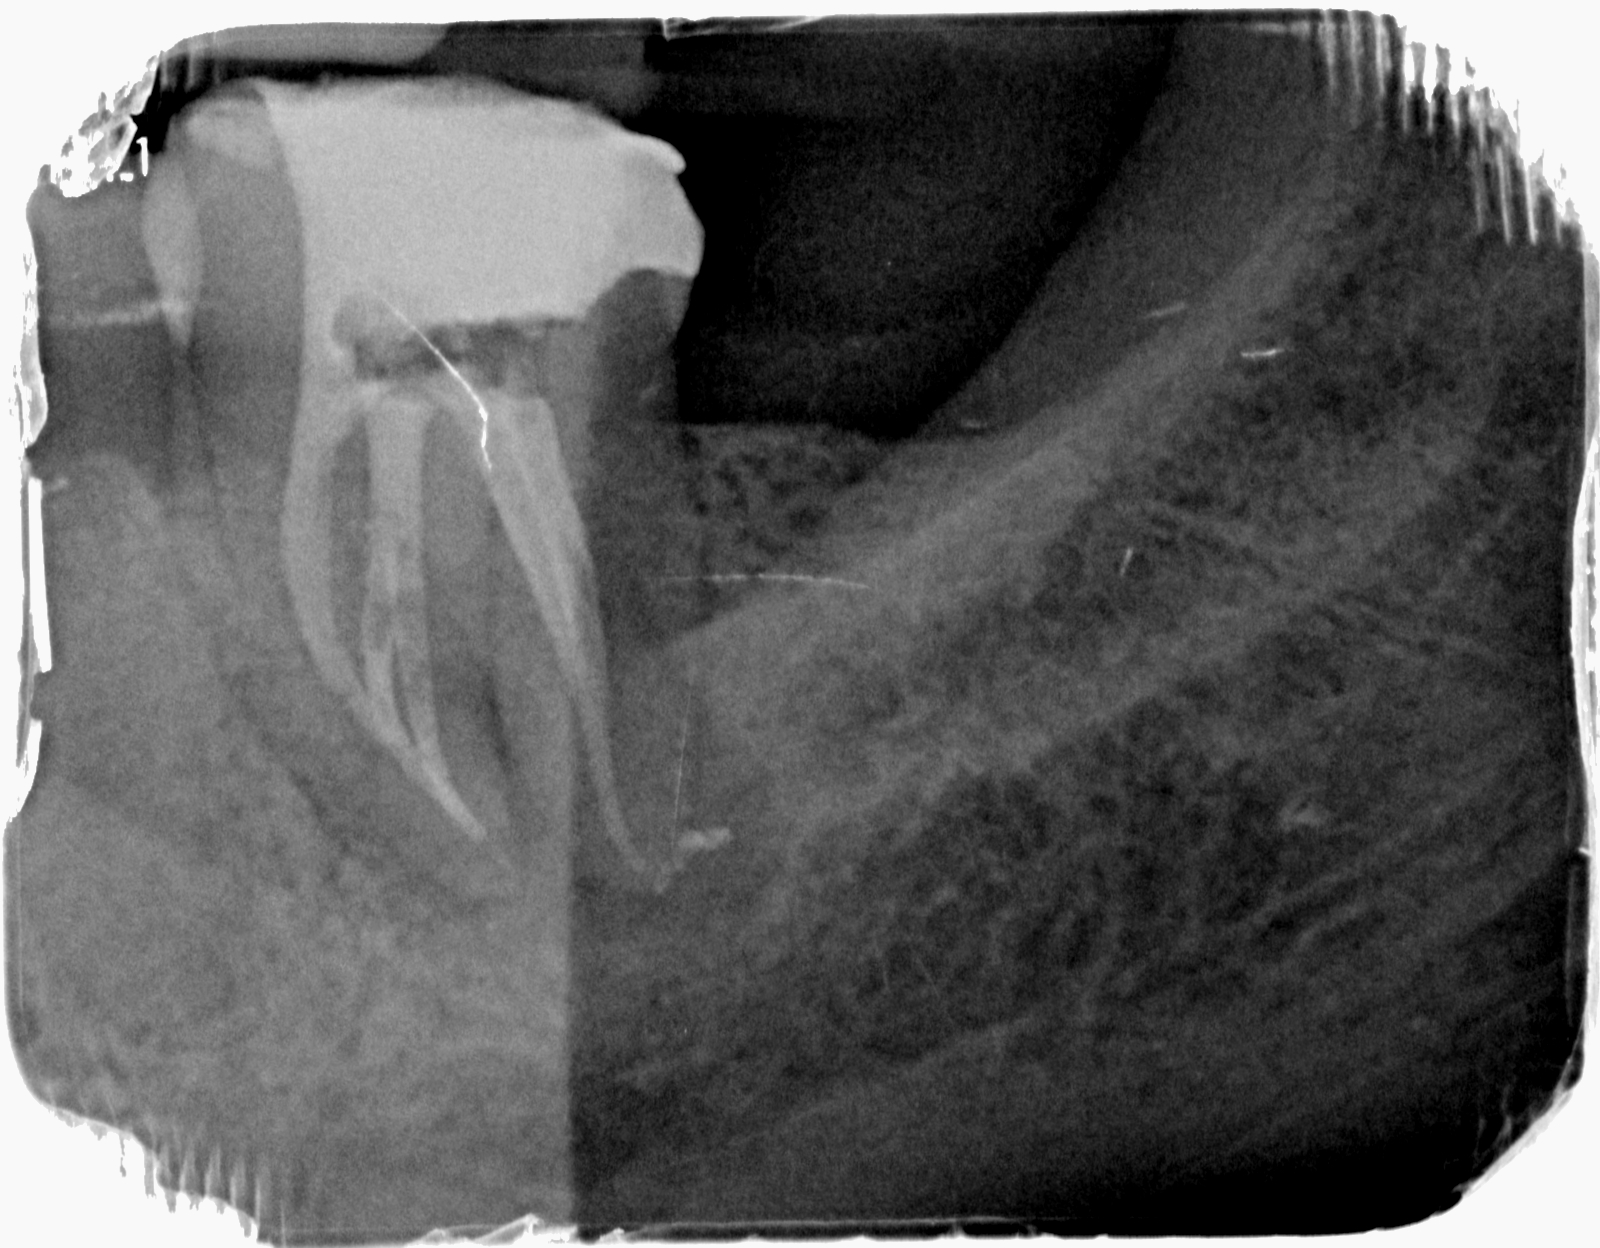

Sellamos la comunicación vestibular con Cavit, realizamos apertura con fresa H7, aislamos con clamp nº9 y localizamos dos conductos, uno vestibular y otro lingual.

Permeabilizamos con limas K#10 y #15 y expandimos el glidepath de forma rotatoria con la lima R-Pilot (VDW). Medimos los conductos con nuestro LEA (En este caso Propex Pixi), obteniendo unas longitudes de 18mm (V) y 19mm (L).

Para la instrumentación del conducto usamos Protaper Next X1 y X2. Una vez instrumentados, realizamos el protocolo habitual de irrigación con NaOCl 4’25%, EDTA 17% y NaOCl 4’25% activado durante 30 segundos por conducto con Endoactivator.

Secamos con puntas de papel, calibramos el conducto, y obturamos con Autofit .06 y condensación vertical en caliente, con el sistema B&L.